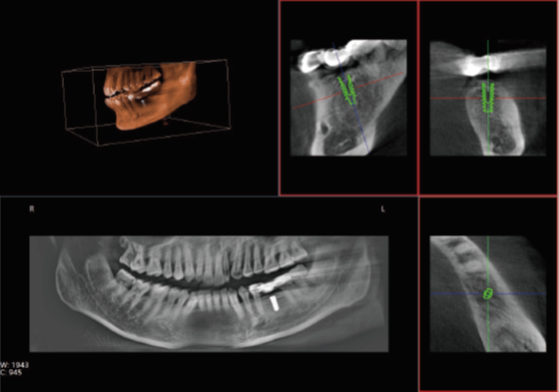

口腔CT是口腔科专用的CT(Cone Beam Computed Tomography), 也就是CBCT,即锥形束CT,采用锥束形X线扫描,可以显著提高X线利用率,只需围绕投照体做环形数字式投照即可获取重建所需的全部原始数据,在计算机中重组,进而获得三维图像。通过数据采集方式的改进,口腔CT不仅提高了医学影像的扫描分辨率,也将放射剂量降低到了一个新的水平。那么,哪些口腔治疗会使用到口腔CT呢?

众所周知,在口腔内种植牙齿是十分精细的手术,没有先进的可视化影像设备支持的种植牙手术,就犹如盲人摸象,手术效果难以预知??谇籆T影像能测量牙槽骨的高度和宽度,估计种植部位,与下颌阻生磨牙相关的低位下牙槽神经管影响颌骨的疾病的病理学评估。

正常情况下,牙齿的排列不在一个平面上, 且具有一定的生理弧度,普通X线往往使图像相互重叠,使图片看不清楚。但是,口腔CT的三维成像对牙体、牙根、牙周膜等微细结构显示更加清晰??梢园镏缴私舛细?,牙根内吸收、根管钙化、牙根结石、牙槽骨退缩等情况,能用于根管治疗前寻找根管,术后评估根管充填情况,评估牙周炎程度及预期治疗效果等。

正畸治疗前的诊断分析是治疗成功的重要步骤,口腔CT不仅能提供头颅侧位和曲断片的信息,还可以评价每个牙齿的排列位置,牙根倾斜度,牙槽骨垂直向、颊舌向的骨量,骨密度等。用于牙列不齐矫正、牙颌面畸形矫正、牙周病辅助正畸。

口腔CT与全身CT相比,具有分辨率高、X射线辐射小、投照时间短、费用低、应用广泛方便、操作简单、可以配合第三方软件获得更多信息等优点。普爱医疗口腔CT使用脉冲透视采集图像,在保证成像质量的基础上,可有效降低患者吸收的辐射剂量。实现数字化三维容积重建,冠状面、矢状面、横断面的类CT成像效果,重建全景影像,选配牙种植系统,满足牙周、牙根管、口腔矫形矫正、牙种植等临床病例提供诊断依据。